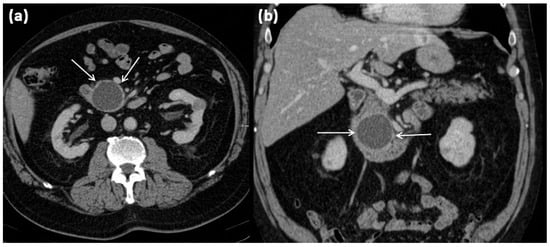

Figure 1.

Axial (a) and coronal (b) contrast-enhanced computed tomography of the abdomen in venous phase in a 74-year-old male patient. In the processus uncinatus, a sharply demarcated pseudocyst (arrows) without solid components, septa, or surrounding infiltration can be seen. At most, the pseudocystic wall shows mild contrast enhancement.